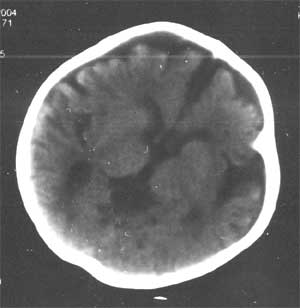

通过脑ct看医生说比较严重 ct检查报告是:右侧基底节区低密度灶,脑沟裂明显增宽,脑室系统清度扩大,中线结构无移位。 ct诊断:1。右侧基底节区缺血性改变 2。脑发育不良

幕上幕下脑室、脑池、脑沟均见扩张积液,考虑脑发育不良。片子质量不好,前囟门似乎偏小,颅骨骨缝不知是否有闭合。9个月幼儿,头围应该不小于40厘米,请测量头围周径。应该没有胼胝体发育不良。至于“右侧基底节区缺血性改变”,片子质量差,看不清楚。

从ct片看1大脑纵裂增宽2侧脑室扩大3蛛网膜下腔增宽 应考虑1胼胝体发育不良,2脑发育不良或萎缩(两周前一般无临床意义应称蛛网膜下腔增宽或外周性脑积水)

粗看:1。双侧额颞顶叶均有不同程度萎缩,脑实质变薄,2。脑室系统对称性扩张,大脑沟裂增宽变深。3。双基底节区未见明确低密灶,胼胝体发育良好。综上所述考虑有:1)大脑发育不良;2)严重脑缺血缺氧性脑病后遗症?个人意见仅供参考。